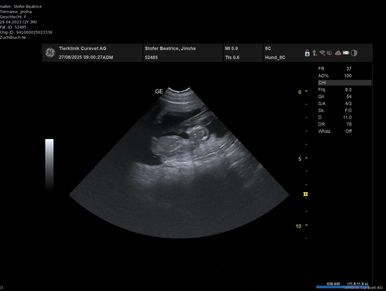

Heute fuhr Stefan mit Jinsha zum Ultraschall. Was wir bereits stark vermuteten, wurde nun bestätigt. Jinsha wird Mamma. Wie viele es sind kann man noch nicht genau sehen. Wir sind sehr glücklich und dankbar.